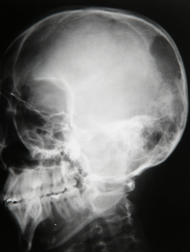

Quais são os 3 tipos de fraturas cranianas?

Linear

Complexa

Com afundamento

Como diferenciar uma fratura linear de marcas anatômicas normais e quais são elas?

Sulcos vasculares e suturas.

A fratura linear tem traço radiotransparente de bordos retos. A região que recebeu maior energia fica com as bordas mais afastadas com afunilamento em direção às extremidades.

Sulcos vasculares tem trajeto tortuoso e apresentam ramificações.

Suturas tem bordas serrilhadas.